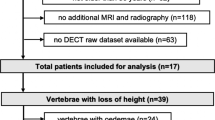

This retrospective study was approved by the local institutional review board (registration number: 62/18S) and was conducted in accordance with the Declaration of Helsinki. Overall, 35 patients were included (80.0% females, mean age: 70.6 ± 14.2 years, age range: 26.2–93.1 years), with 23 patients (65.7%) showing at least one vertebral fracture (fracture group) and 12 patients (34.3%) showing no vertebral fracture (control group). Eligible patient cases were identified in the institutional digital Picture Archiving and Communication System (PACS) between November 2016 and November 2017.

Inclusion criteria were (1) availability of routine MDCT of the spine (irrespective of the initial suspected diagnosis or distinct clinical symptoms leading to MDCT), (2) additional spinal magnetic resonance imaging (MRI) performed prior or subsequent to MDCT (including short-tau inversion recovery sequences; only for the fracture group), and (3) diagnosis of at least one vertebral fracture according to MDCT (only for the fracture group). Exclusion criteria for both the fracture and control group were (1) age below 18 years, (2) movement artifacts in imaging data, (3) malignant bone lesions (e.g., bone metastases), (4) any history of metabolic bone disorders aside from osteoporosis, and (5) any implants captured by the field of view (FOV).